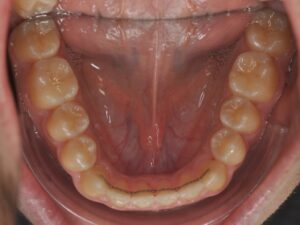

- d’un fil collé sur la face interne (linguale) des dents

- de gouttières passives de stabilisation réalisées sur mesure. `